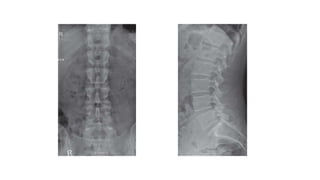

Thoracic spine

X-ray in AP and Lateral

projections.

Vertebral body (star ) of

T12 with rib hypoplasia;

T10–T11 intervertebral

foramina (circle ); T11

right pedicle(arrowhead )

Thoracic spine X-ray inAP and Lateral projections. Vertebral body (star ) of T12 with rib hypoplasia; T10–T11 intervertebral foramina (circle ); T11 right pedicle(arrowhead )